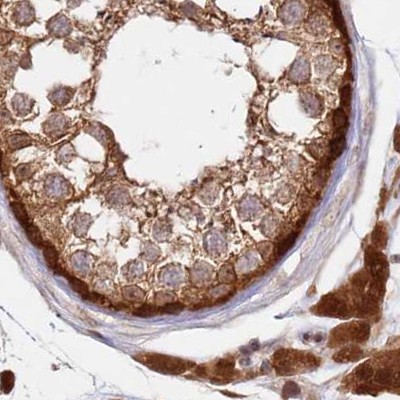

Immunohistochemical staining of human colon, kidney, liver and testis using Anti-GBE1 antibody HPA038075 (A) shows similar protein distribution across tissues to independent antibody HPA038074 (B).